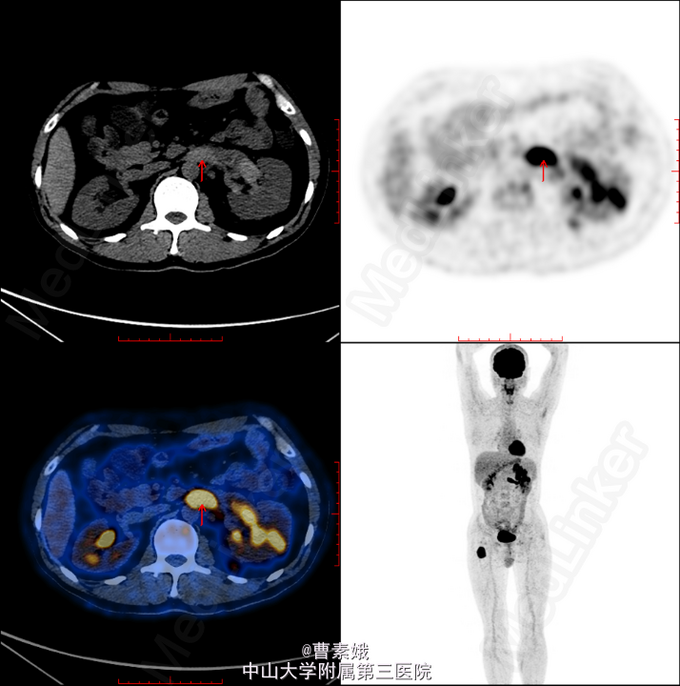

初步诊断:右股骨近端骨肿瘤(?)。 考虑右股骨肿物性质未明,遂于我院行全身PET/CT及腹部CT增强扫面,检查结果提示:1、左肾肿块并左肾静脉充盈缺损,代谢活跃,考虑左肾癌(透明细胞癌可能)并左肾静脉癌栓形成;双侧肾上腺座椅;腹膜后淋巴结转移;左侧股骨 经济股骨上段骨转移。随后患者行“左股骨肿物+左肾肿物穿刺活检术”,冰冻病理结果提示:左肾透明细胞癌,左股骨肿物考虑肾透明细胞癌转移。考虑患者肾透明细胞癌多发转移,无手术指征,转入肿瘤内科予索坦靶向治疗。